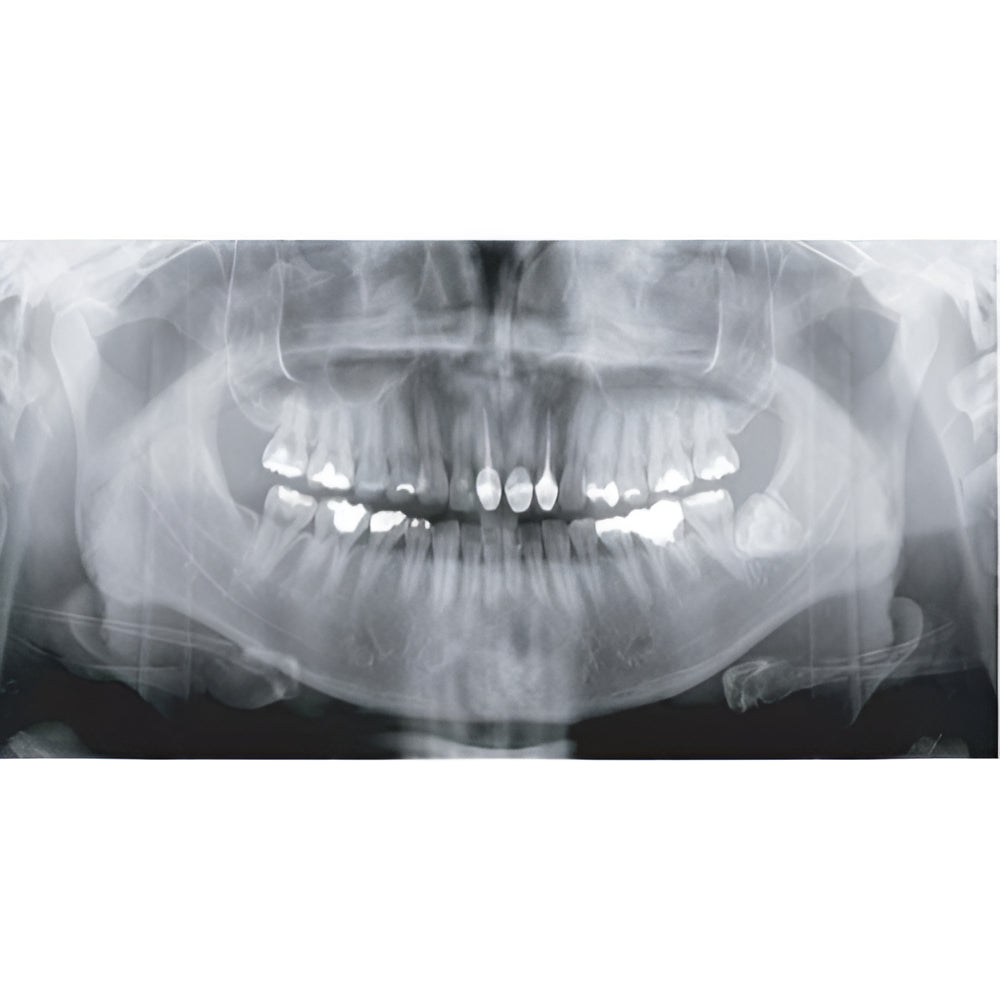

Papaya uses the CdTe sensor, which improves image quality while keeping radiation exposure to a minimum. The CdTe (Cadimium telluride) sensor overcomes the limitations of a CMOS sensor to always produce high quality images.

- Field Of View: 4x5, 7x7, 8x8, 14x8, 14x14

- Panoramic